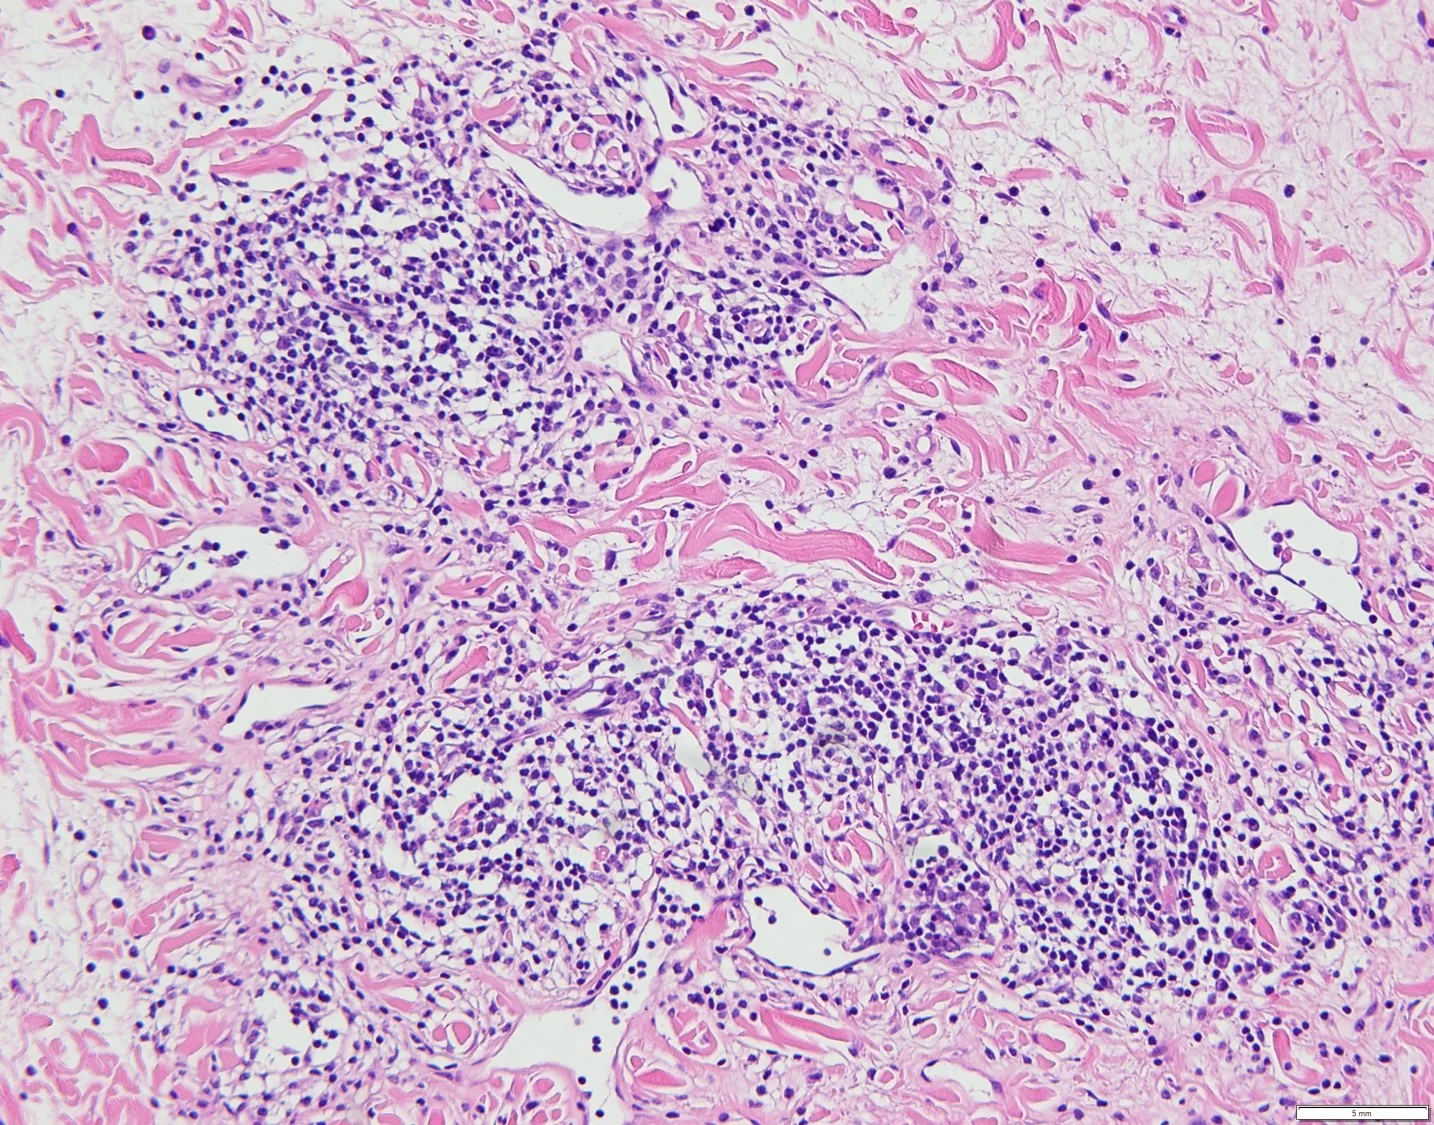

Case 3A: A Unique Case of Extranodal NK/T-Cell Lymphoma Mimicking Mycosis Fungoides

Casregivers: Michael James Davis, BMus, Dipti Anand, MD; Atlanta, GA

History: An 80-year-old Caucasian gentleman with no significant past medical or drug history presented with multiple acute and rapidly progressing lesions. No systemic symptoms such as fever, malaise or weight loss were reported.

Physical Exam: Exam revealed several 1-3 cm well demarcated, erythematous and violaceous plaques on both sun exposed and non-sun exposed aspects of the patient’s extremities and abdomen. No facial involvement was noted. Deep punch biopsies of the right anterior thigh, right posterior arm, and right anterior arm were performed.

Laboratory Data: ANA -, Anti Ro -, Anti La -, ESR 2.

Histopathology: The sections showed a dense superficial and deep perivascular, perifollicular, and interstitial lymphoid infiltrate extending into the subcutaneous tissue. The lymphocytes were pleomorphic, intermediate to large, with irregular chromatin distribution and scattered mitoses. The overlying epidermis demonstrated subtle interface vacuolization with scattered single and collections of lymphocytes, suggestive of epidermotropism. There was no significant necrosis or vasculitis, but extravasation of erythrocytes with riming of fat by atypical lymphocytes was seen.

The histologic differential diagnoses included plaque and tumor stage mycosis fungoides, pseudolymphomatous lupus panniculitis, cytotoxic subcutaneous panniculitis-like-T-cell lymphoma and primary cutaneous gamma/delta T cell lymphoma.

Immunohisochemical evaluation revealed tumor cells to be positive for CD2, CD3, CD56, TIA-1, and granzyme B, and negative for CD5, CD7, CD4, CD8, CD20, and CD123. Additionally, CD 30, Beta FI Gamma M1 were also negative. EBV-encoded RNA (EBER)-1 in situ hybridization was positive for EBV mRNA. RT-PCR T-Cell gene arrangement study was positive.

The histology and staining profile were consistent with EBV positive Extranodal NK/T-Cell Lymphoma.

Clinical Course: Systemic workup for nasopharyngeal and extra nodal site involvement was recommended at a tertiary care center.

Diagnosis: Extranodal NK/T-Cell Lymphoma.

Points of Emphasis: Beyond the classic presentation of an ulcerated mid facial tumor, previously coined “lethal midline granuloma,” Extranodal NK/T-Cell Lymphoma requires a high index of suspicion for accurate diagnosis. Following the nose and upper aerodigestive tract, the skin is the most commonly involved site. Lesions are typically plaques or nodules, at times ulcerated; vasculitis and panniculitis presentations can also occur. The infiltrate is usually angiocentric and may be angiodestructive with variably sized tumor cells.

Immunophenotypically, the tumor cells express CD2, CD3ɛ, CD56, TIA-1, and granzyme B. EBER in situ hybridization is the most reliable test for confirming the presence of Ebstein-Barr Virus which is detected in almost all cases. Extranodal NK/T-cell lymphoma presenting in the skin is a highly aggressive tumor with a median survival of less than 15 months.

Our patient presented with a unique clinical and histologic manifestation of this uncommon lymphoma. Clinically, the lesions mimicked lupus panniculitis and mycosis fungoides, and lacked the tumor nodules and ulceration, often seen in this lymphoma. The histology also posed a challenge, simulating mycosis fungoides and pseudolymphomatous lupus erythematosus. The lymphoma lacked the necrosis, prominent angiocentricity and angiodestruction, and high mitotic rate with apoptosis, which is classic for this neoplasm. Epidermotropism as noted in our case is seen in ~30% of these tumors.

It is important for both clinicians and pathologists to be aware of this uncommon cutaneous T-cell lymphoma, which can mimic mycosis fungoides both clinically and histologically. Awareness of this entity is important for its prompt recognition and treatment.